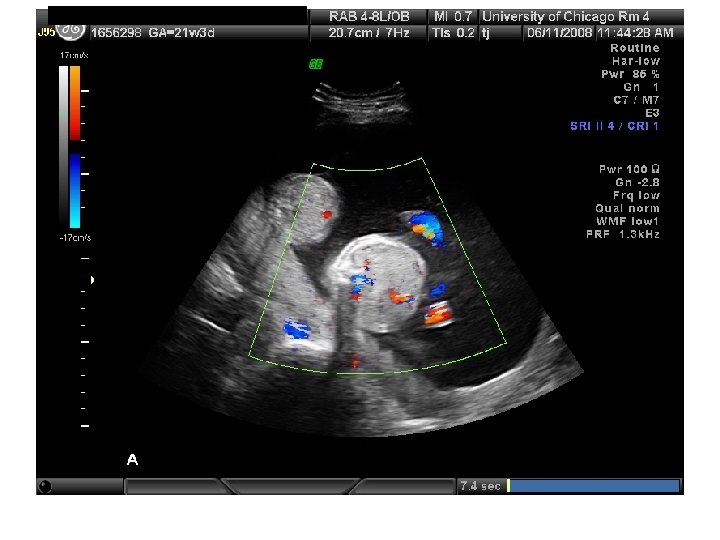

QUIZ What is Your Diagnosis? Case: Patient J. F. 30 years old, at 32 week gestation. Presented with the following pictures.

Answer: a) Trisomy 21 b) Non-immune Hydops c) Paravo virus Infection